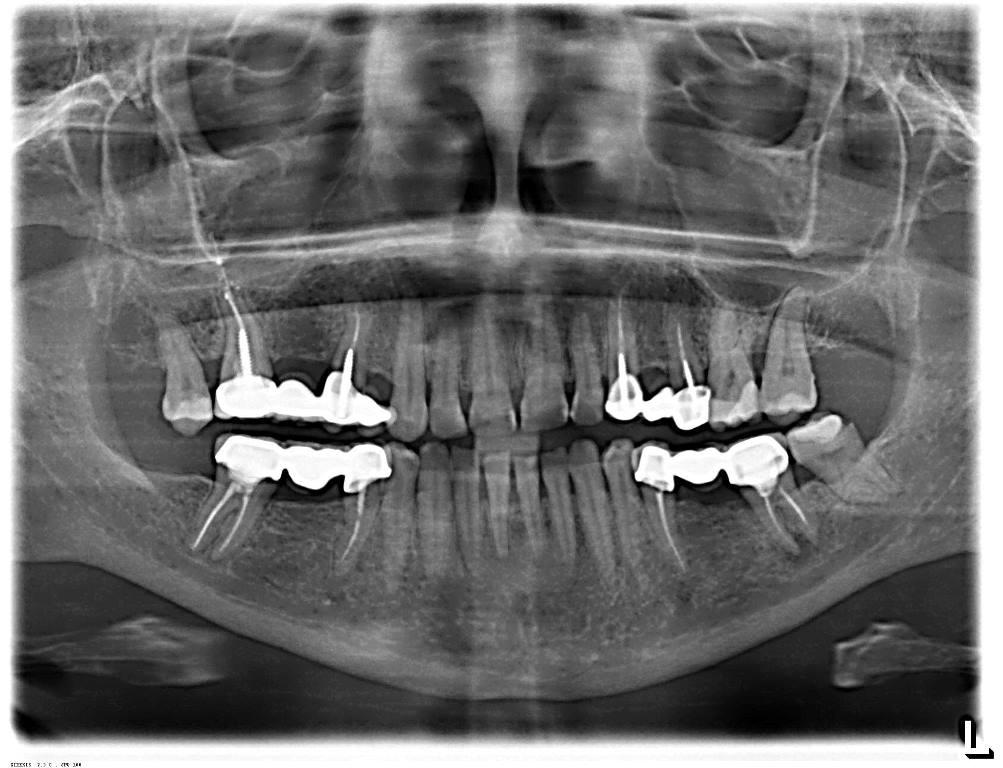

Примеры ортопантомограмм и их анатомия

Раздел: Фотоэссе